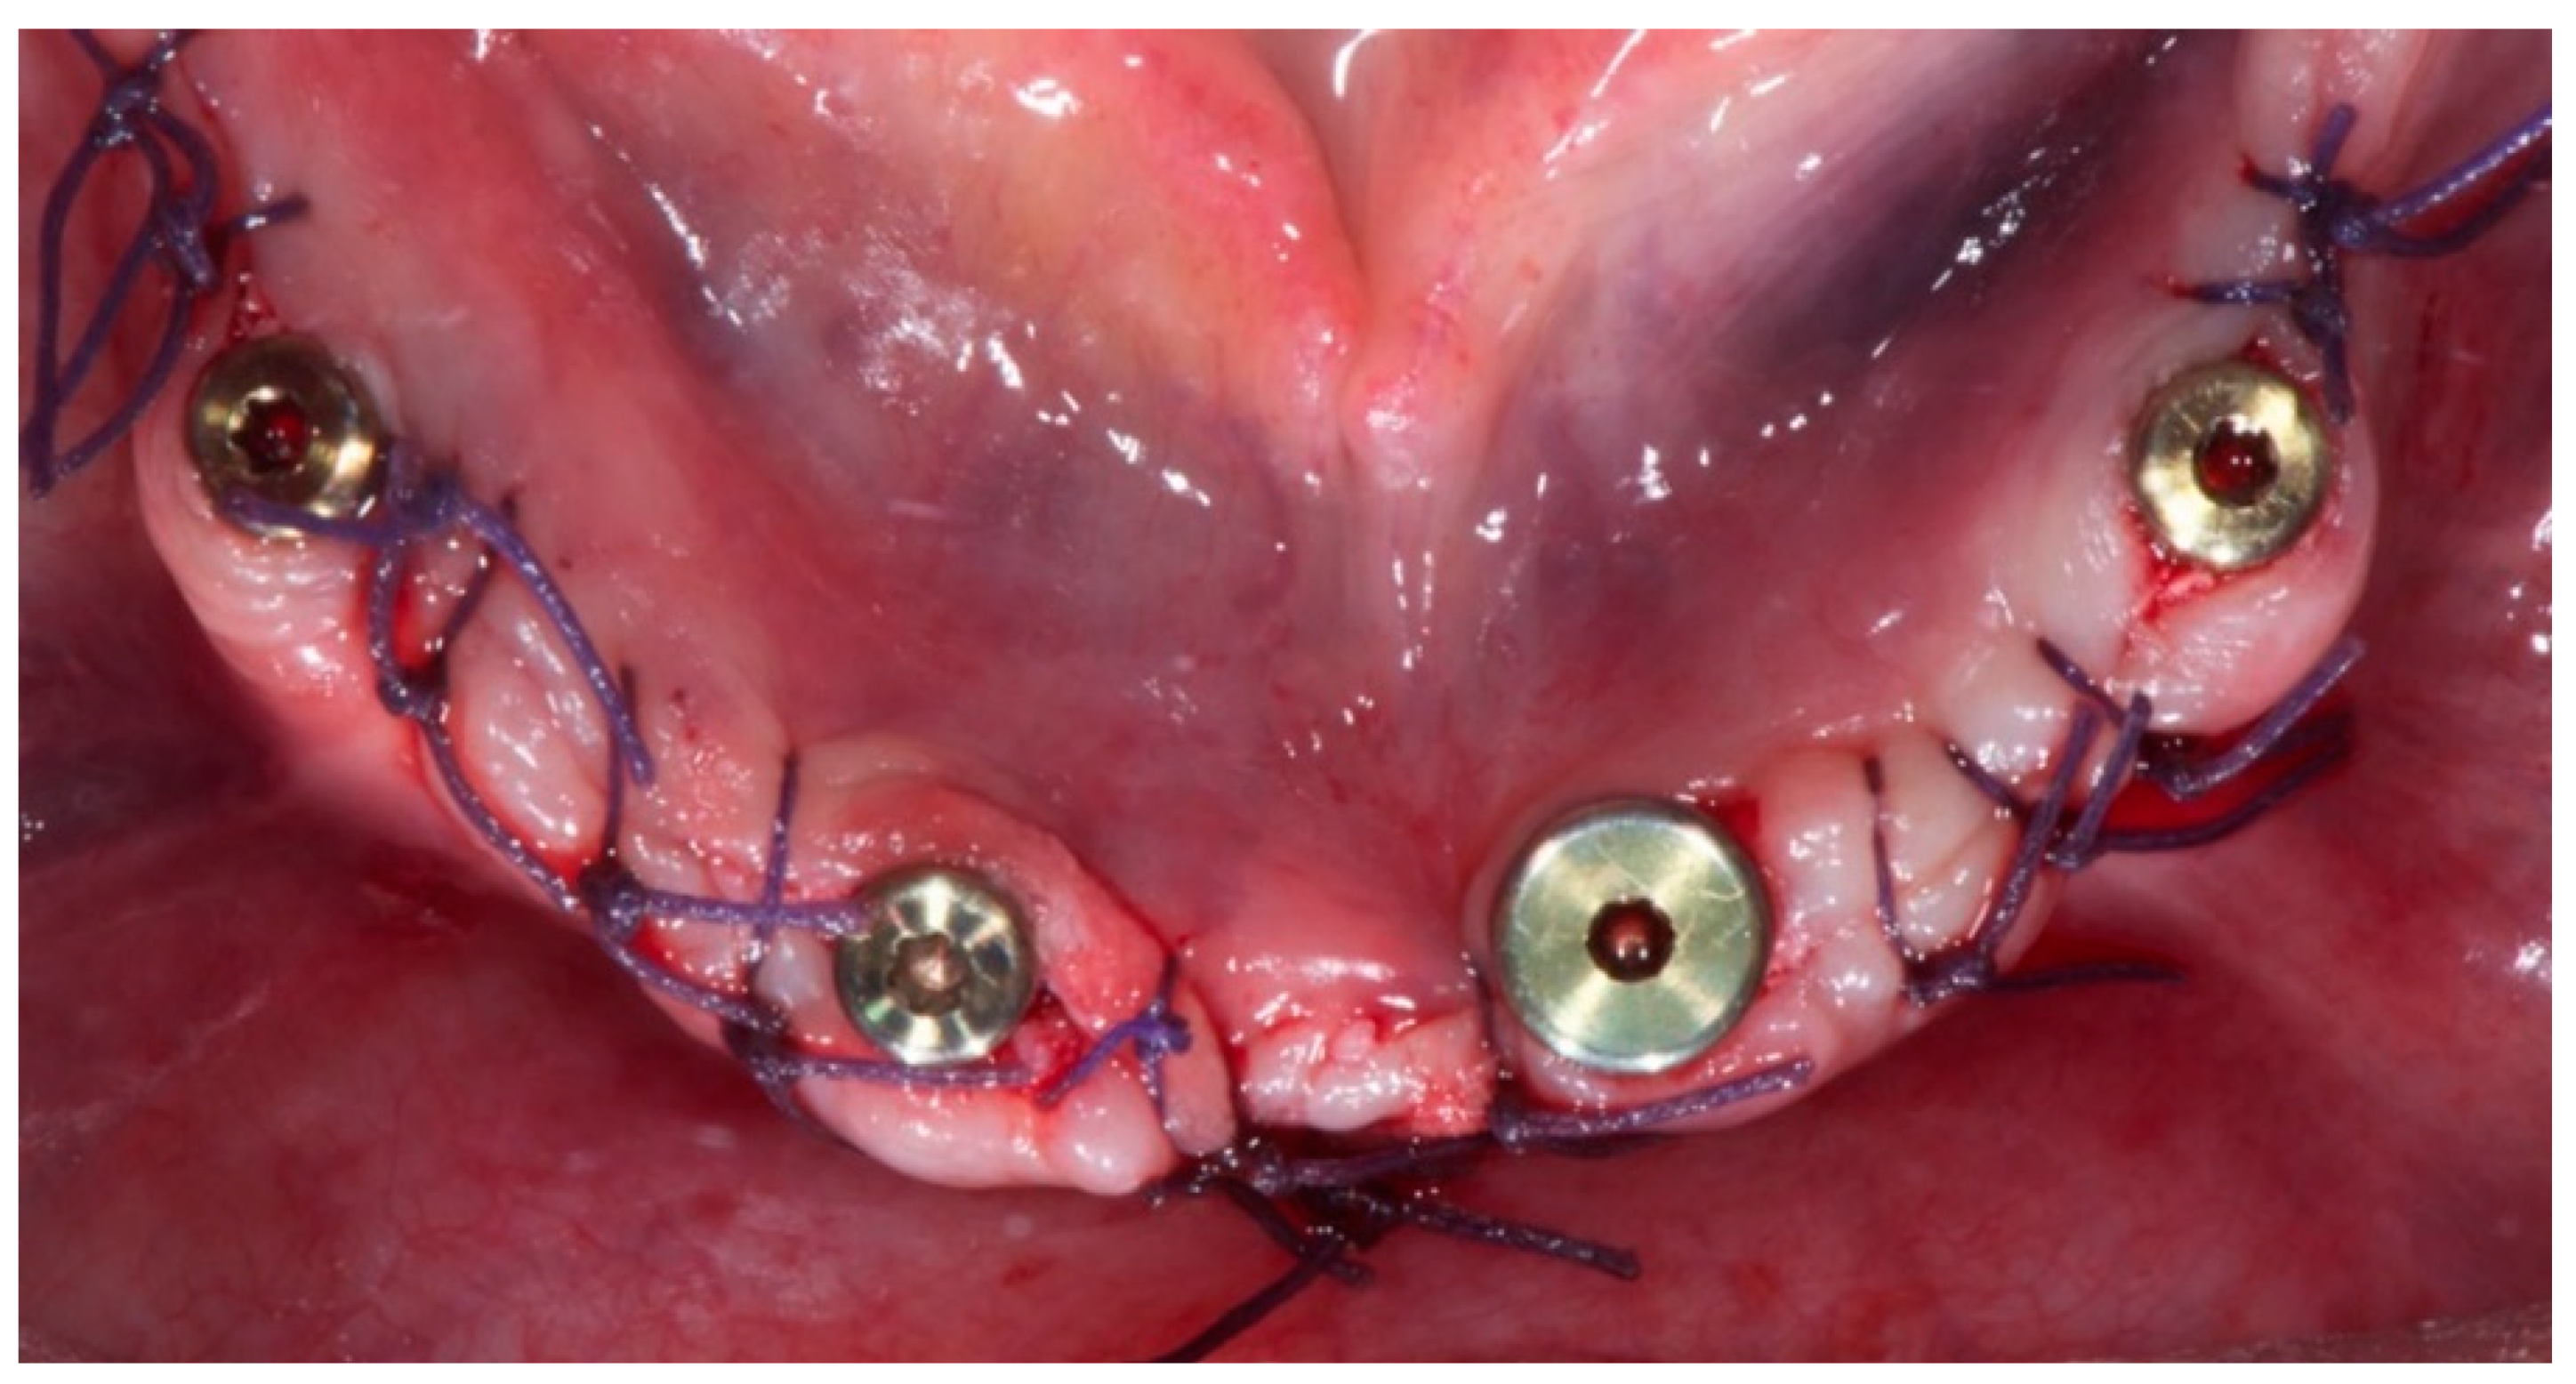

2. Materials and Methods